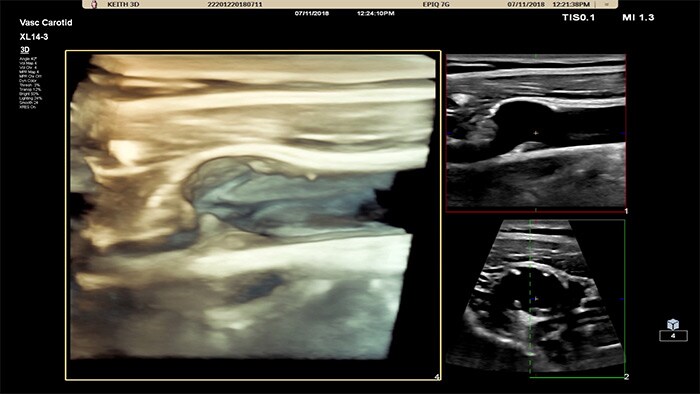

O XL14-3 xMATRIX também permite visualizar a anatomia em 3D/4D incríveis com um fluxo de trabalho guiado por ICON de fácil utilização. Os médicos conseguem olhar diretamente para um vaso para avaliarem a localização espacial e a composição das placas e ver os dados de fluxo 3D para avaliarem as condições estenóticas ou tortuosas.

A interface do utilizador 3D/4D também oferece a capacidade de gerar um molde do vaso utilizando dados do fluxo. A fundição de vasos 3D permite a visualização direta do fluxo para análise adicional da estenose ou condições tortuosas. O principal benefício: a visualização 4D/3D de alta qualidade da anatomia vascular proporciona uma ferramenta de comunicação ideal para facilitar as decisões clínicas entre os profissionais de saúde e melhorar a consulta com os pacientes para ajudá-los a compreender a sua condição.